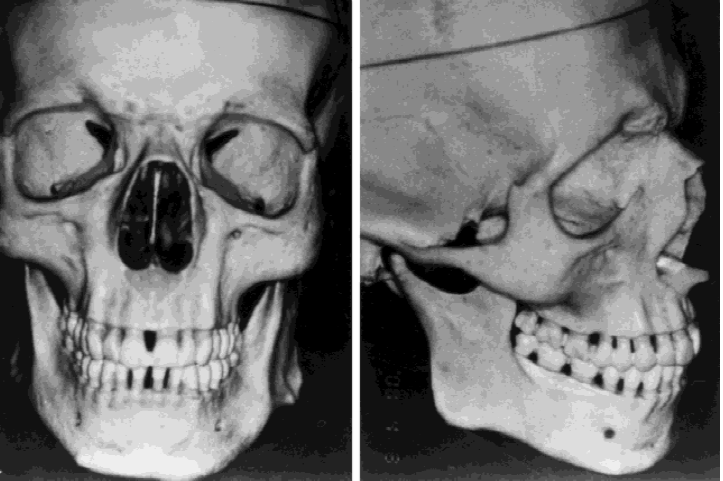

What is the anterior nasal spine?

The ANS is the small bone that sticks out at the very base of your nose, between the nostrils:

Seen from the front:

The ANS is the small bone that sticks out at the very base of your nose, between the nostrils:

Seen from the front:

- Bone cut shaped like a "U" around the piriform rim that mobilizes the anterior maxillary wall and ANS as one segment. The segment is advanced, rotated, and fixed with small screws.

- Projects the ANS and paranasal rims forward.

- Why vs graft/implant: Uses actual bone for a cleaner contour. Likely superior to both implants and especially grafts if done right.